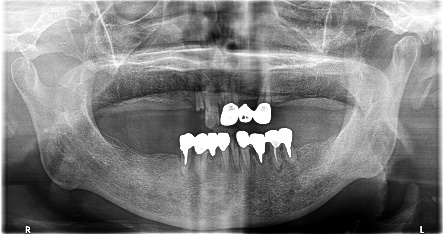

上下、歯がないところに入れ歯を作ったが、使っていない。インプラント治療をしてほしい。

治療内容

上顎4本残っている歯を抜歯し、インプラントを6本埋入。下顎、右下2本、左下1本埋入。

所感

上顎3本は、もし義歯で対応する場合であれば、保存してマグネット義歯の支台として活用します。しかし、患者さんが義歯ではなくインプラント治療を希望され、かつ、見た目が自然でよく嚙めるようになることが最優先事項でしたので、相談したうえで3本の歯は積極的に抜歯しました。

治療後、「インプラント治療に満足しています。食事が楽しくなりました。スタッフの方の説明がわかりやすかったです。1年間ありがとうございました。」と、とてもうれしくなる感想を書いていただきました。

上顎:全額治療 ¥3,280,000(税込)

下顎:インプラント3本 ¥363,000×3本=¥1,089,000(税込)

合計:¥4,369,000(税込)

Before

After